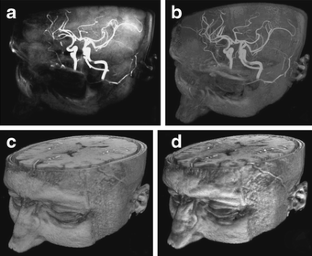

Fig 1.